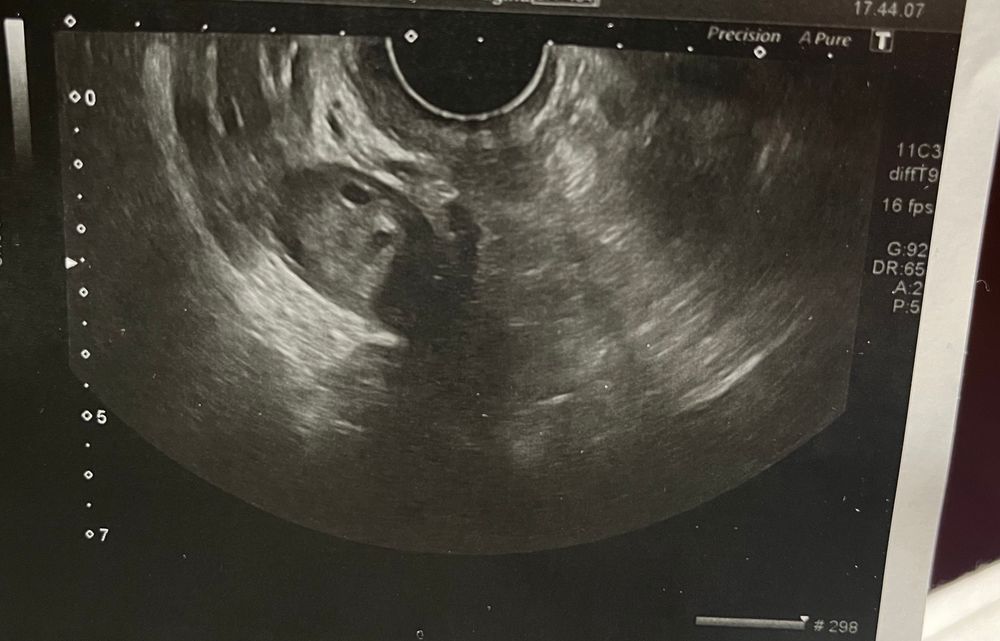

Ниже приложу один из снимков узи где по моему что-то есть странное хотя узист сказал что всё хорошо и ничего нет